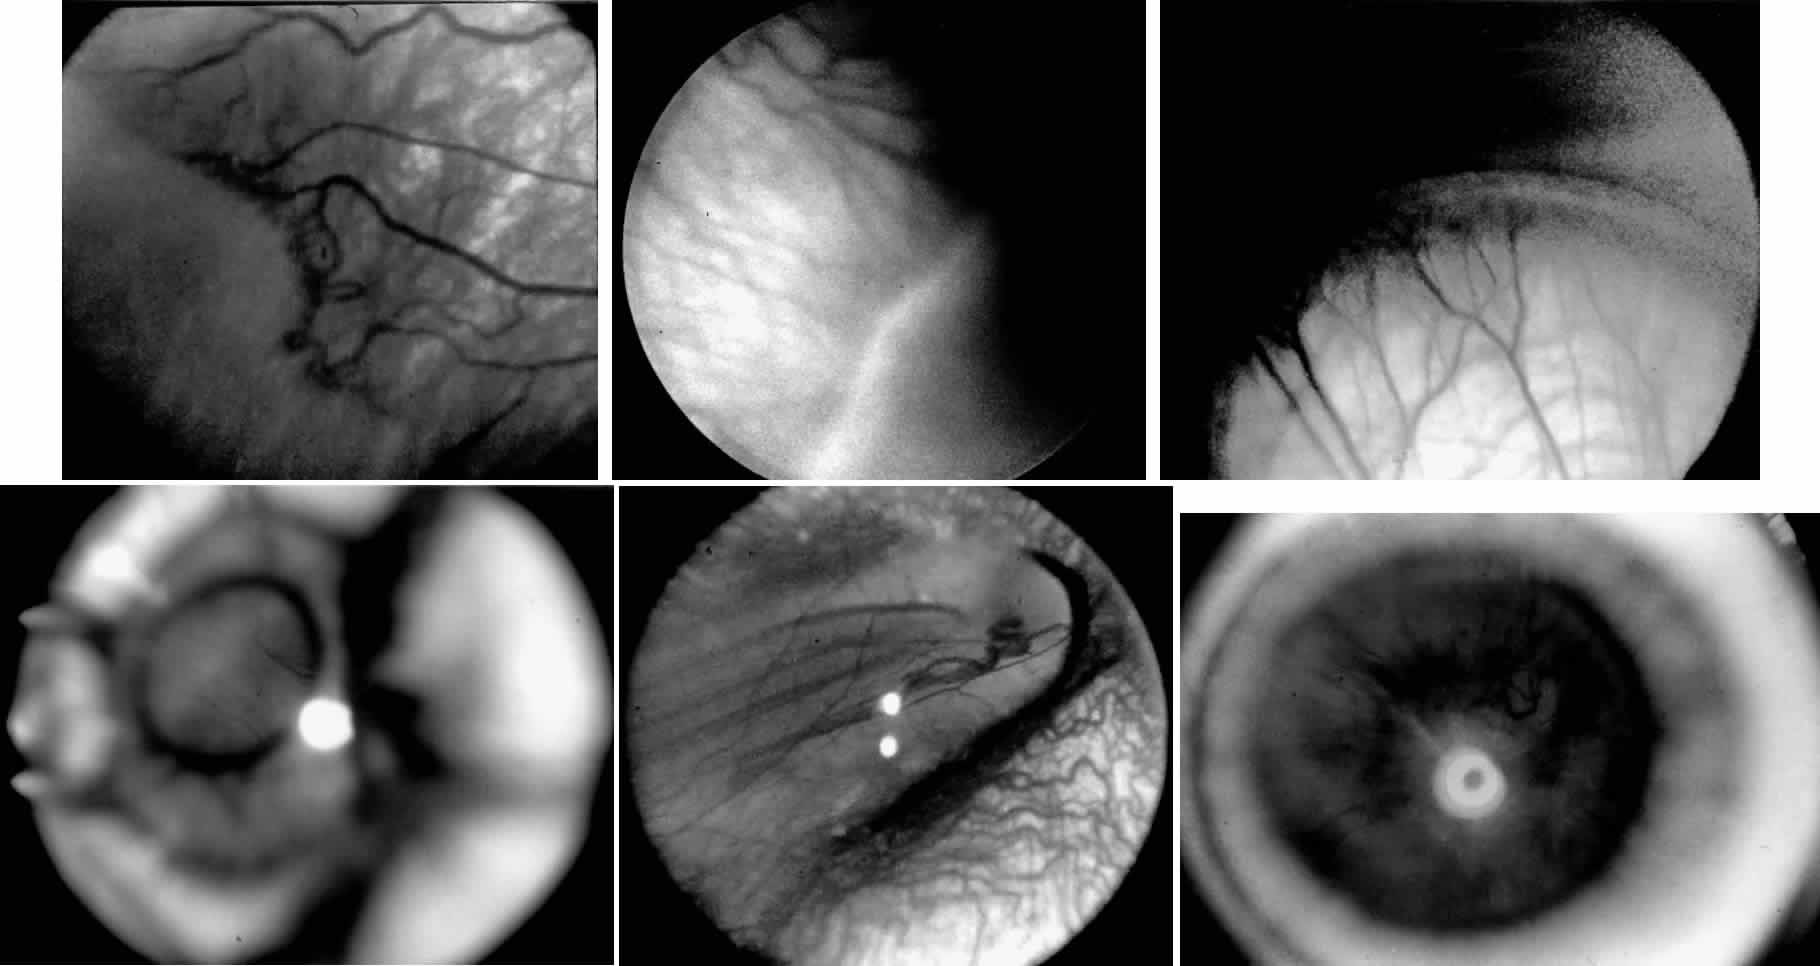

ROP accounts for a large number of retinal detachments in the pediatric population. The International Classification of Retinopathy of Prematurity helped greatly to improve communication about, and consequently treatment of, ROP. It describes affected eyes in terms of stage, zone, and absence or presence of plus disease18 (Figs. 1, 2, and 3). Screening of premature infants is an important feature in the care of ROP, which is perhaps the most significant and enduring finding of the Cryotherapy for Retinopathy of Prematurity Study (Cryo-ROP Study).19

Fig. 1. Stages of retinopathy of prematurity. A. Stage 1, showing a small white line visible between the avascular and vascularized retina. B. Stage 2, with the junction showing a wider white line between avascular and vascularized retina. C. Stage 3, with frank neovascularization extending into the vitreous cavity from the area posterior to the retinal ridge. D. Stage 4A, showing peripheral retinal detachment with the macula attached. E. Stage 4B, with a partial retinal detachment with the macula detached. F. Stage 5, showing total retinal detachment.